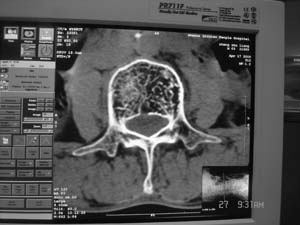

以下是引用余辉在2008-4-27 17:12:00的发言:[br]骨质疏松伴病理性压缩性骨折,椎骨骨松质密度减低,椎体骨小梁稀疏且普遍呈火柴头样改变,椎体无膨胀,无软组织肿块

以下是引用mzh123在2008-4-27 19:33:00的发言:[br]除压缩骨折表现外 还有许莫氏结节改变

以下是引用随光逐影在2008-4-27 21:29:00的发言:[br]除压缩性骨折外,还有许莫氏结节及骨质疏松表现。